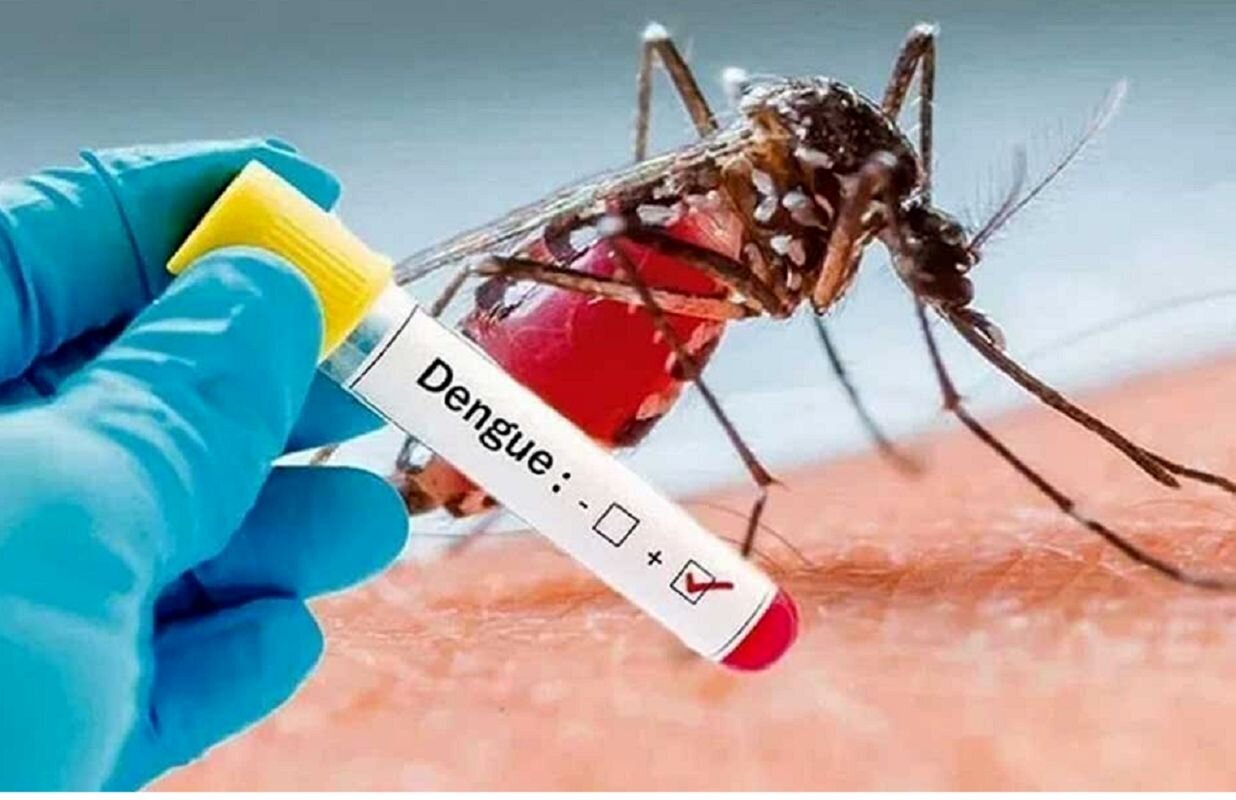

تب دنگی خطرناک شد/ واکنش وزارت بهداشت

آفتاب نیوز : ماجرای پشه آئدس و بیماری تب دنگی از بهار و تابستان امسال دوباره بر سر زبان ها…